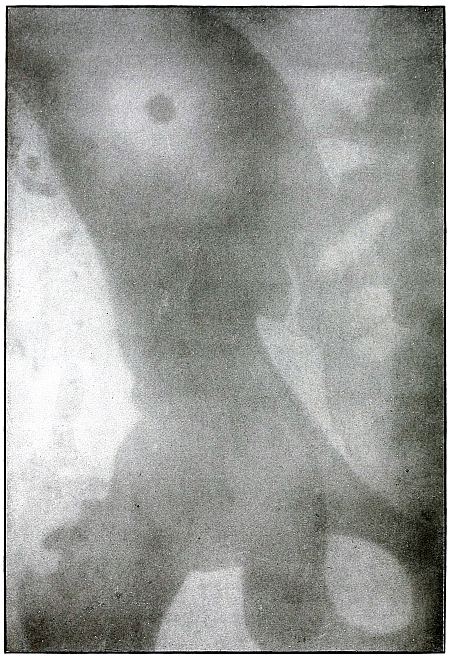

LOWER EXTREMITY.

Plate 47.

[Pg 105]

Rifle—Plate 47.

LOWER EXTREMITY.

Gunshot Wound of the Gluteal Region,

with Lodgment of the Bullet Near the Ischium.

Wound of entrance, over gluteal prominence on a transverse line

through the great trochanter.

Wound of exit, none.

There was no bone injury in this case. The bullet, to have lodged in

the soft parts after relatively slight penetration, must have struck

the body at extreme range when its energy was almost spent in flight,

for its normal outline indicates that it was not retarded by ricochet.

The long axis is almost perpendicular to the plate. As the posterior

pelvis was next to the plate, the fairly dense shadow shows the

projectile was not far from the plate and behind the ischium.

The treatment is conservative; infection in such cases is extremely

rare; and only pain or impaired function after many months of

convalescence justifies operation for removal of the missile.

[Pg 106]

Plate 48.

[Pg 107]

Rifle—Plate 48.

LOWER EXTREMITY.

Gunshot Wound of the Thigh,

with Lodgment of the Bullet.

Wound of entrance, outer aspect of the thigh at the junction of the

upper and middle thirds.

The slight penetration without bone injury and with slight deformity

of the nose of the bullet indicates that the wound was caused by a

ricochet shot at extreme range, after its energy was almost spent.

With the posterior aspect of the thigh next to the plate, the dense

shadow and the nearly normal size of its outline indicate that the

bullet was in the same relative position and that it lay posterior to

the neck of the femur.

As such wounds are rarely infected, the treatment is conservative,

and a search for the missile is only justified by serious infection,

pain, or impaired function.